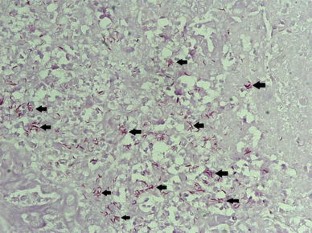

The mean age was 38.24 ± 11 (range 15–64) years. Elevated levels of serum CA125 were determined in all 28 patients (100 %). Other common findings were ascites in 20 (71.43 %, 20/28), pelvic mass in 21(75 %, 21/28), slight fever with night sweat in 13 (46.43 %, 13/28), cough and pleural effusion in nine (32.14 %, 9/28), high fever more than 39 °C combined with abdominal pain and elevated white blood count in five (17.86 %, 5/28), weight loss more than 5 kg at admission in six (21.43 %, 6/28). Diagnoses were made based on biopsy from laparotomy in 14 (50 %) patients, from laparoscopy in nine (32.14 %), from diagnostic curettage because of primary infertility in two (7.14 %), and only from clinical suspicion in three patients. Histopathology revealed that caseating granulomatous lesions were seen in 25 patients, positive anti-acid staining in 11 patients. Totally 26 patients completed anti-TB therapy successfully and were cured, two patients died of the disease because of long-term immune inhibitor used.

Fig. 1–3